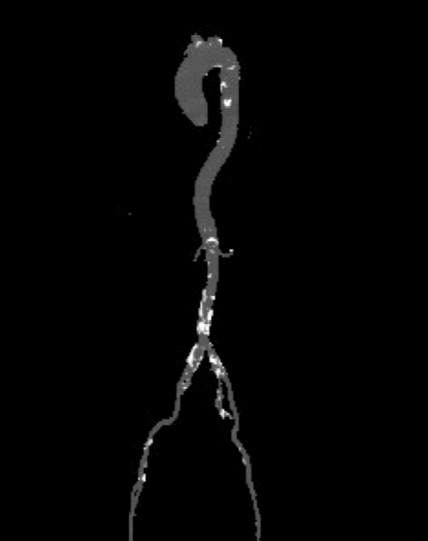

主动脉根部测量

ANNULUS

SOV DIAMETER

LVOT

STJ

瓣环水平夹角

LEFT VENTRICLE

CT数据显示该患者为三叶式主动脉瓣。

主动脉瓣瓣环周长66.2,平均周长径 21.1mm,SOV:32.2mm*36.4mm*34.1mm,瓣叶增厚,瓣上钙化分布不均,主动脉瓣环水平夹角67度,横位心。

冠脉高度测量

LEFT CORONARY

左冠开口高度16.9mm

RIGHT CORONARY

右冠开口高度16.0mm

钙化分布

左心室影像

外周血管及主动脉弓解剖